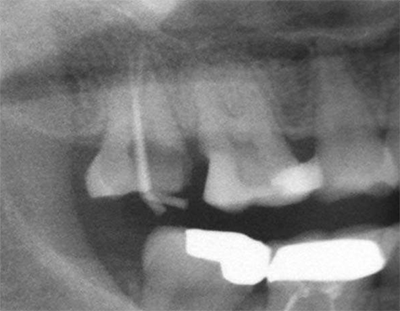

术前X-ray

术前X-ray局部放大图